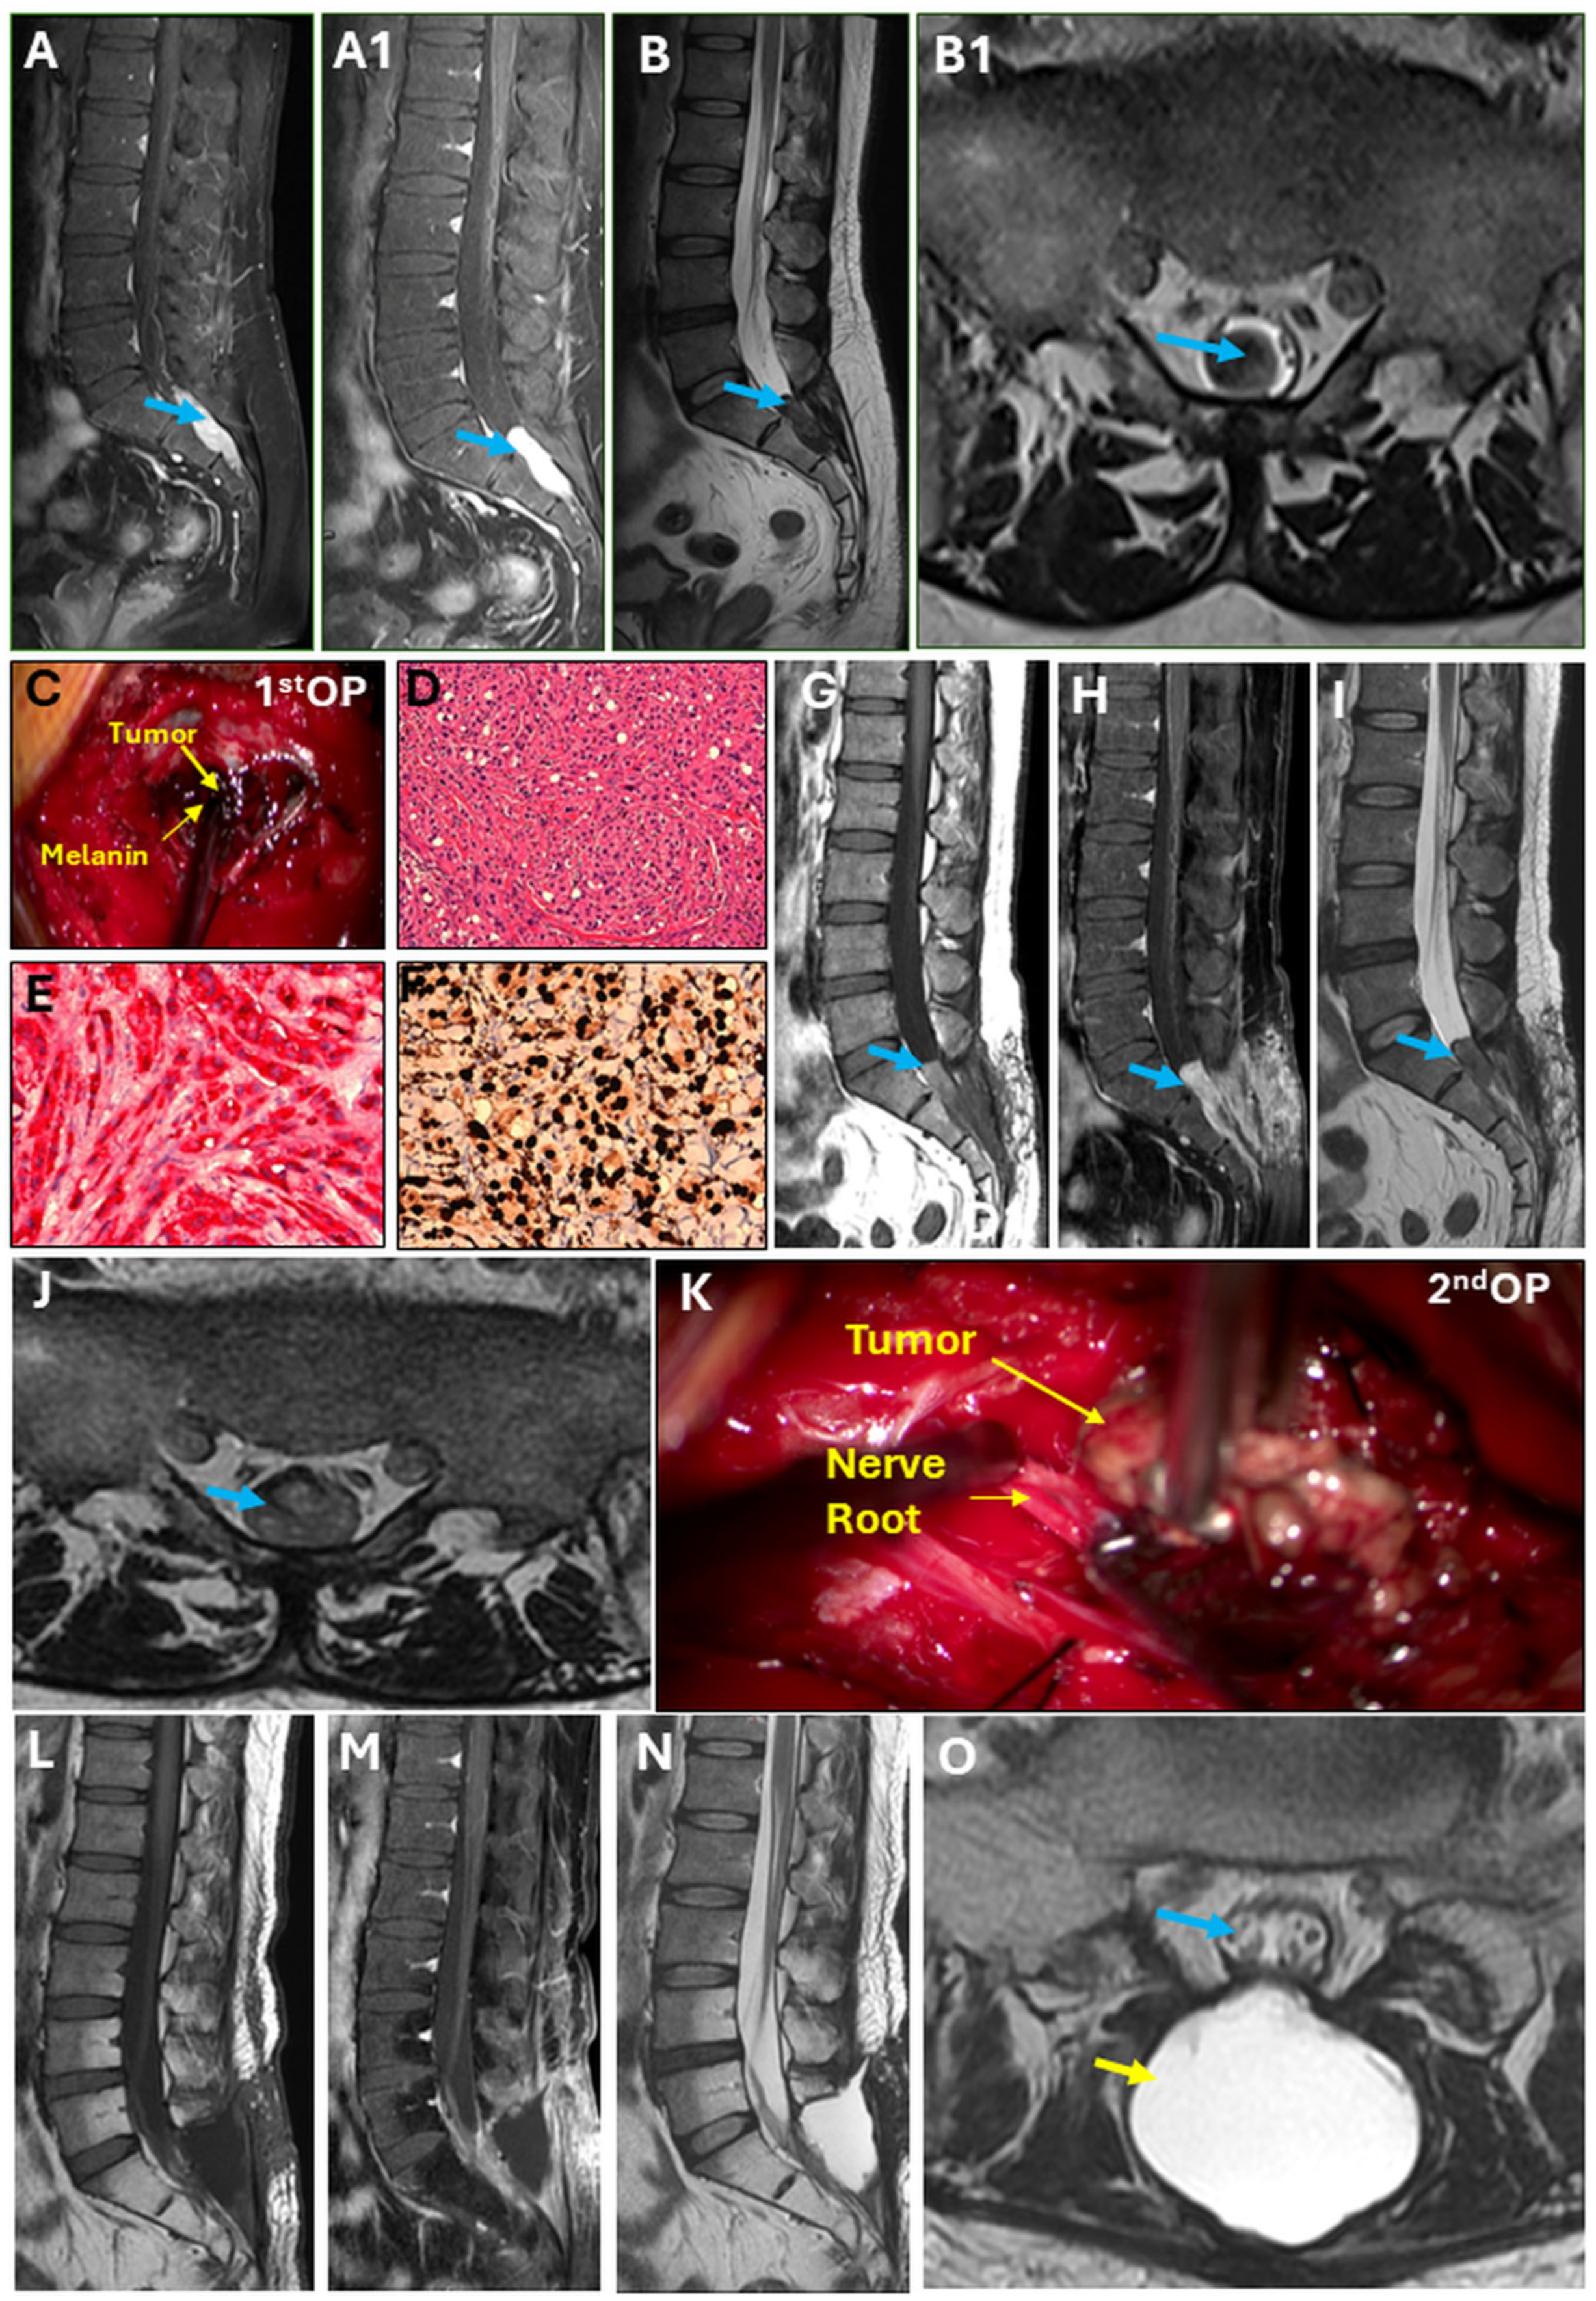

2. Detailed Case Presentation

Surgical Technique